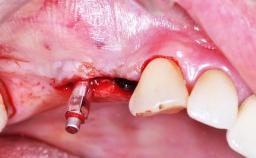

- Details of surgical techniques for SFE

- Recent advances regarding the SFE techniques